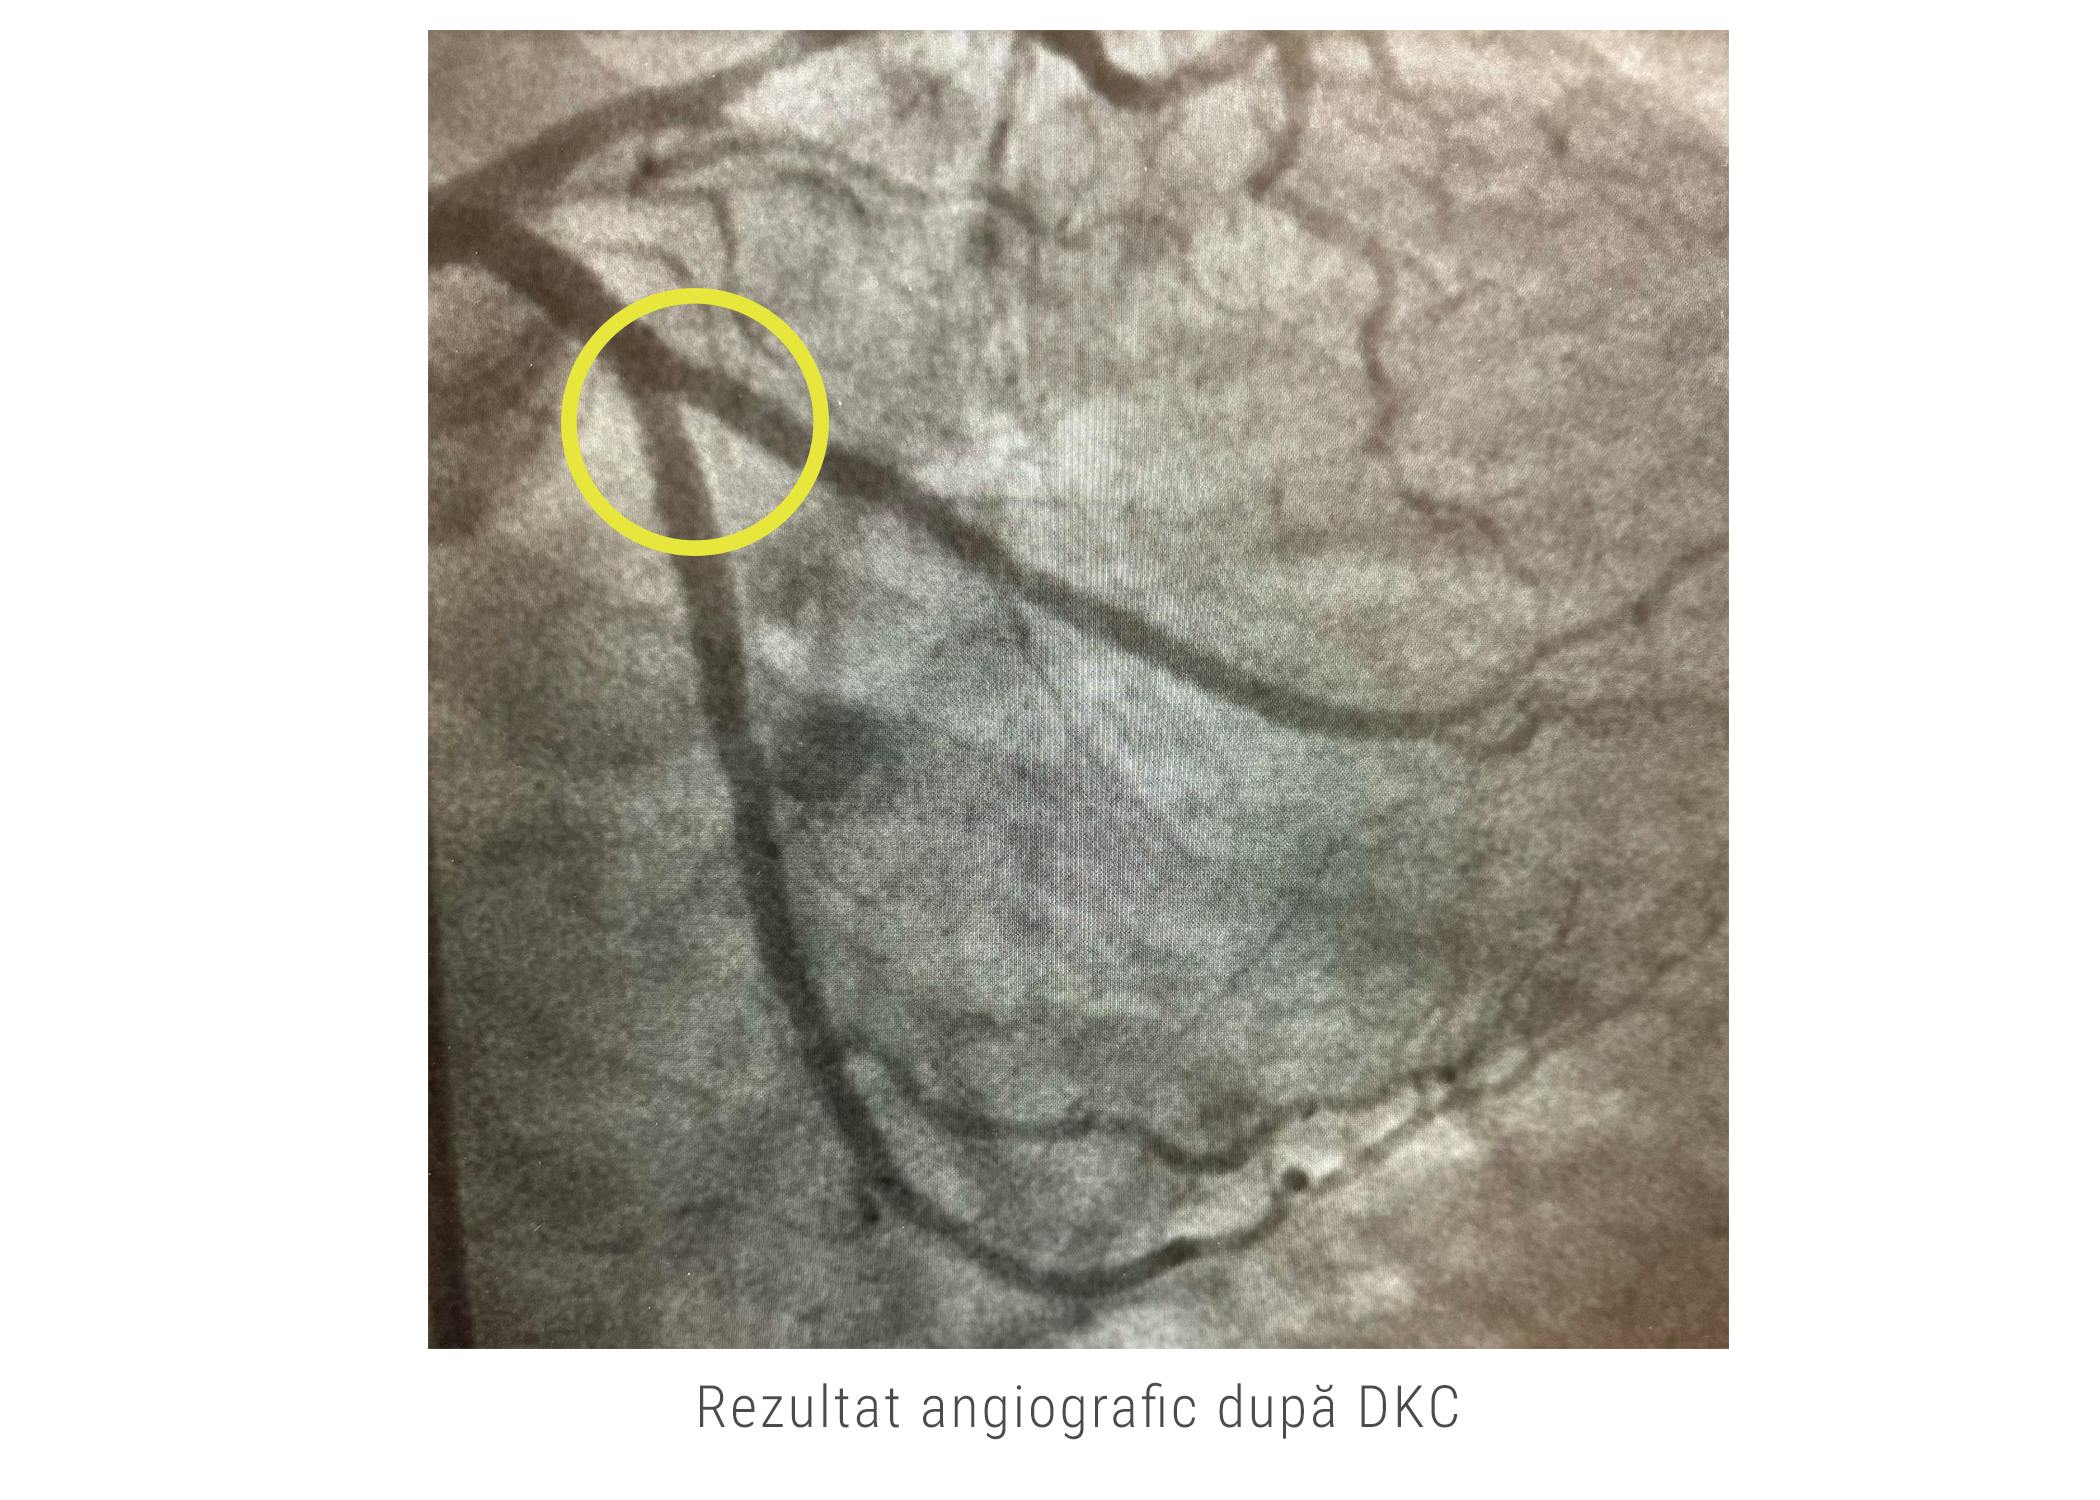

În cazul acestei paciente, pentru a îi salva viața, dr. Nicolae Cârstea și dr. Adnan Mustafa au folosit o tehnică avansată numită “double kissing crush”. În timpul acestei tehnici, medicii au umflat simultan două baloane în cele două ramuri ale bifurcației, implantând, ulterior, cele două stenturi. Tehnica a fost executată cu succes, circulația la nivelul bifrucației a fost redată așa cum se poate observa din imaginile alăturate.

Rezultatul procedurii este foarte bun, pacienta este în afara oricărui pericol cardiac și urmează să fie externată cu recomandări medicale și mențiunea să revină la controale cardiace periodice pentru a evita un astfel de eveniment cardiac major.